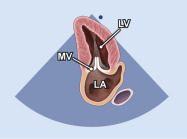

| 2.1. Mặt cắt trục dài cạnh ức với depth sâu

Cửa sổ siêu âm cạnh ức

Mặt cắt trục dài cạnh ức Đầu dò đặt tại bờ trái xương ức với marker hướng lên vai phải của bệnh nhân. |

Khoang màng ngoài tim Khoang màng phổi | |||||